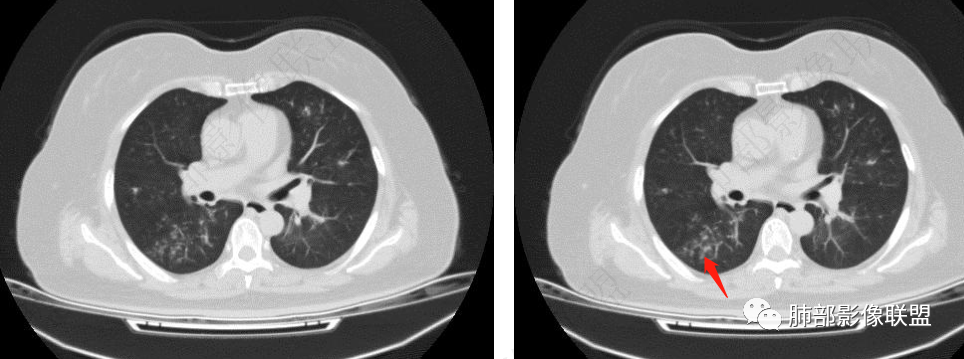

影像上是否有肺出血呀?感觉肺动脉周围有渗出,气道曲霉然后血管侵犯入血?

老年女性,发现白细胞升高两年,此次入院多次查外周血白细胞>30*10^9/L,淋巴降低,CRP显著升高,但病程中无发热,以细菌性炎不好解释;CT提示有脾大,结合外周血象,首先考虑存在血液系统疾病(白血病)基础,且未系统诊治;肺部CT提示双肺中轴间质增粗,伴随支气管管壁增厚?多发树丫及腺泡结节,部分呈点晕征,可见肺动脉分枝增粗,一元论考虑白血病肺部浸润;二院论考虑白血病并发气道侵袭曲霉。以患者病程进展看,更倾向于白血病肺部浸润。

肺动脉增粗,支气管有改变

左侧腔内有粘液栓,右侧支气管局部有扩张

支持气道病变,弥漫,支气管壁增厚,糖尿病,支持霉菌